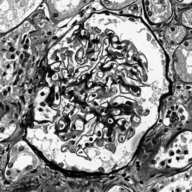

Image datasets in digital pathology applications often consist of consecutive slides stained differently, each staining providing specific information on the same region of interest (see Figure 1, first row). Even though differently stained slides appear very different, there is often a significant amount of consistent information between them. For example, they may both share the same counterstain (e.g. haematoxylin), or they may highlight different parts of the same structure.

The analysis and integration of information from different stainings is usually performed with reference to a specific organ, structure, or pattern observed in the tissue. For example, to diagnose pathologies such as breast cancer or kidney allograft rejection it is necessary to study the inflammatory micro-environment of the organ. In these cases, the relevant information is the distribution of immune cells (e.g. macrophages or lymphocytes) in relation to important structures of the organ, such as glomeruli for the kidney, or lobules for the breast.

Objects to be segmented, e.g. glomeruli, are generally easily identified between stainings as globally they exhibit the same structure and texture, see Figure 1. It should therefore be possible to bias the network to learn stain invariant features. This work investigates this possibility by modifying the data presented to the network in an unsupervised manner. Borrowing domain adaptation terminology, herein the staining used for training and validation is referred to as as the source staining (irrespective of any transformations), and the stainings to which the network are applied as target stainings.

N.B. the intention is to present plausible colour profiles to the network. This does not necessarily correspond to biologically relevant image information but is explored for any potential for the tested staining modalities. Potential limitations are addressed, e.g. in Figure 1 the bright red colour (chromogenic reaction used to detect CD34, a marker of blood vessel inner lining) could be successfully transferred but it is not localised as in the original image.

Next is a strategy to extract biological information that is consistent across different stainings—the haematoxylin counterstain. Despite this biological plausibility, it does not result in good results. Indeed, the haematoxylin transformed images vary greatly between the different stainings (see Figure 1, second row). Several factors may explain this: 1) haematoxylin’s concentration relative to the primary stain may vary from one staining to another, resulting in different shades of blue and fixation amount; 2) as a counterstain, haematoxylin may become mixed with another stain in structures that are targeted by both. These result in a color mixing that is in practice not perfectly unmixed by a color deconvolution algorithm.